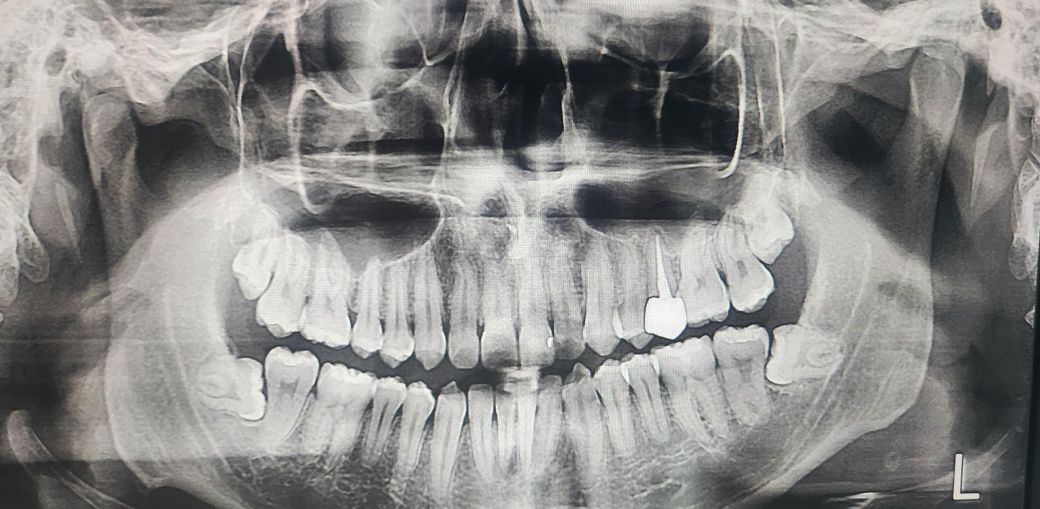

딱딱한걸 씹고난뒤 왼쪽 상단 어금니가 통증이 생길때가 있는데요

치과에 가보니 맨끝 어금니가 휘어있고 사이에 음식물이 잘 끼여서 통증이 있는거다 라고 하셨습니다 그래서 별다른 조치없이 시간지나면 낫는다고 하시길래 괜찮아졌었는데 딱딱한걸 씹다보면 음식물이 또 끼거나 외상이 생겨서인지 통증이 반복되네요

혹시 사랑니가 밀어서 그런가 싶어서 말씀드려보니 그럴수도 있는데 사랑니 뽑기에는 아직 이르다고 하셨었고요

현재로서는 교합평가를 먼저해야 합니다. 금이 가거나 잇몸 질환이 있지 않고 충치도 없는데 증상이 있다면 교합(아래 위 치아가 씹히는 위치)을 평가하여 과도하게 힘이 가해지지 않는지, 아래 치아가 위에 치아를 과도하게 특정한 방향으로 밀지 않는지 등에 대한 평가가 필요합니다. 다만 교합 평가를 하기 위해서는 현재 사진으로는 불가능하며 교합지나 t-scan 등을 활용하여 확인을 해보아야 합니다.

치간 사이 식편이 들어가는 것은 명확한 해결책은 없습니다. 음식물이 끼더라도 잘 관리하면서 빼내는 것이 가장 상책이며 상악 사랑니는 맹출 양상 좀 더 지켜보신뒤 발치하시는 것이 좋아보이며 하악 사랑니의 경우 매복된 상태로 발치 고려하심이 좋아보입니다.